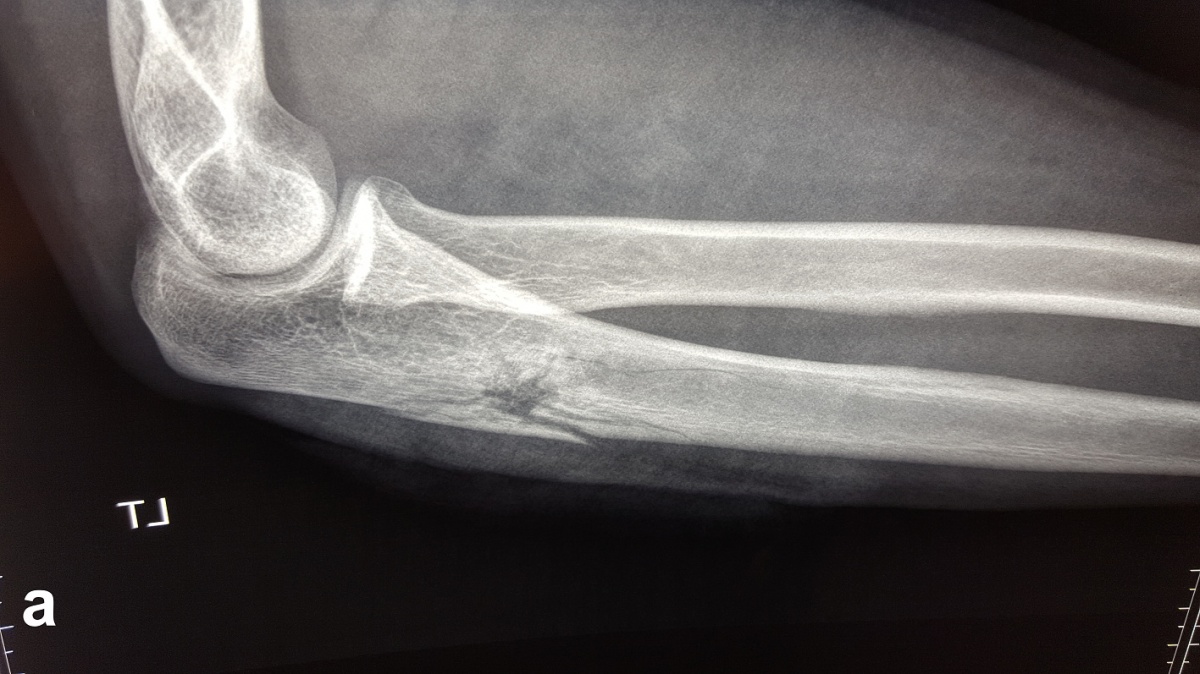

Beim Auftreffen des Projektils im Rahmen von Niedrigenergieverletzungen auf Knochengewebe entsteht meist eine typische, einfache Fraktur (Abbildung 2). Hochenergieverletzungen des Knochens münden in eine multifragmentäre Situation, bei der ein Großteil der Projektilenergie an den Knochen abgegeben wird. Insbesondere lange Röhrenknochen können, da sie wie eine starre, spröde flüssigkeitsgefüllte Röhre agieren, durch Projektile mit hoher Energie explosionsartig zerstört werden (Abbildung. 3).

Nach Steckschussverletzungen, insbesondere durch Niedrigenergiegeschosse, stellt sich Frage, ob das Projektil entfernt werden muss (Abbildung 5). Ist das Projektil nicht zu tasten und liegt es im Weichteilgewebe außerhalb von Gelenken, kann es durchaus belassen werden [1]. Bei Projektilen in Gelenken ist die Entfernung anzustreben, da durch sekundäre Schäden bei Bewegung durch Abrieb der Gelenkfläche auftreten können [1]. Zudem ist eine Bleiintoxikation durch in den Gelenken verbliebene Projektile möglich [51, 52].